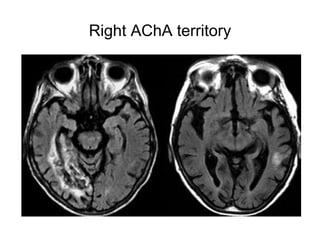

Right AChA territory

• Occasionally, the territories of supply of the

lenticulostriate arteries may be the only regions

that undergo infarction in MCA stroke .

• When occlusion of the MCA occurs distal to

the MI segment (and thus distal to the origins of

the lenticulostriatearteries), infarction in the

cortical territory of the MCA may occur without

infarction of the basal ganglia.